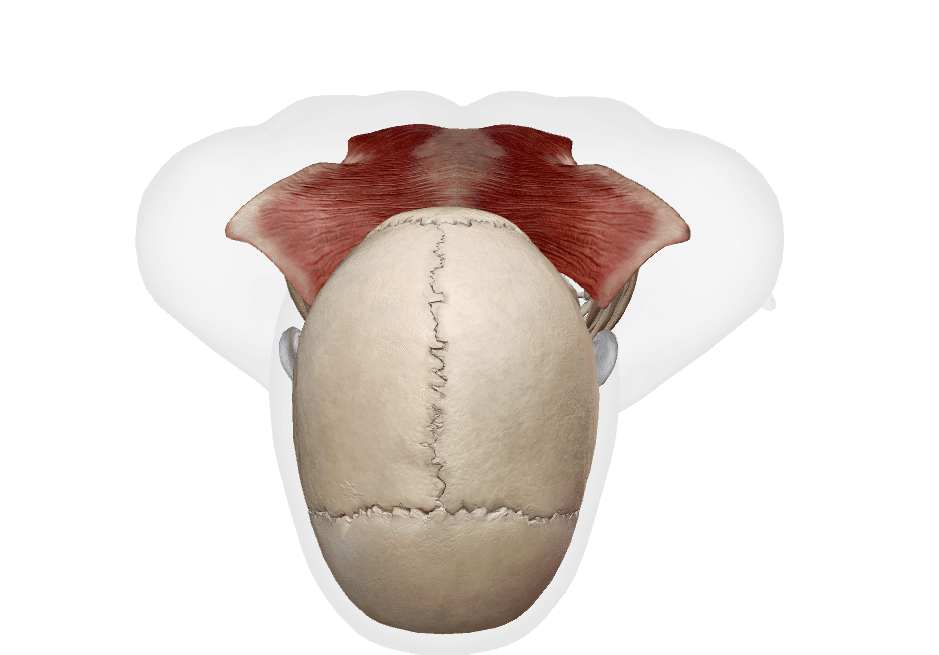

起始

後頭骨

項靭帯